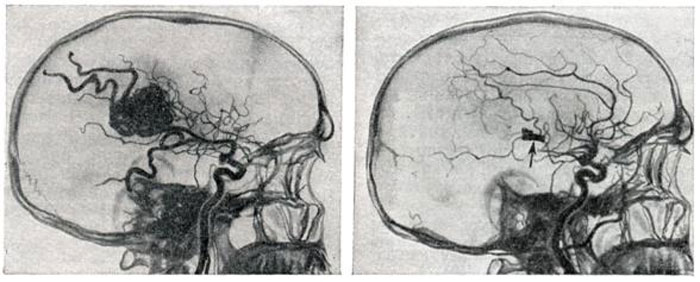

Хирургические процессы при эмболизации гемангиомы на фото

Раздел: Снимки-откровения